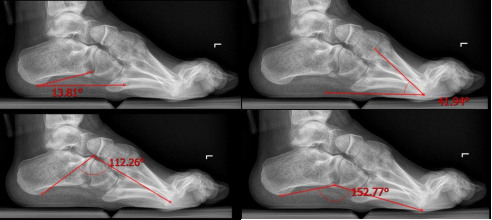

腓骨肌萎缩症是一种罕见病,2018年5月国家卫生健康委员会等五部门联合制定《第一批罕见病目录》中使用该名称。腓骨肌萎缩症主要是由于遗传因素出现下肢的渐进性活动性障碍,由于肌肉肌力的变化,导致足部及踝关节活动出现异常,手术治疗的原则是纠正足部畸形,重建和平衡足踝肌力。手术方案包括肌力平衡手术(各种类型的肌腱转移术)、软组织松解与矫形(足底筋膜切开术)、跟骨截骨矫形、腓肠肌复合体处理、踇趾矫形或其他足趾矫形手术。手术治疗有利于恢复患者的生活质量。